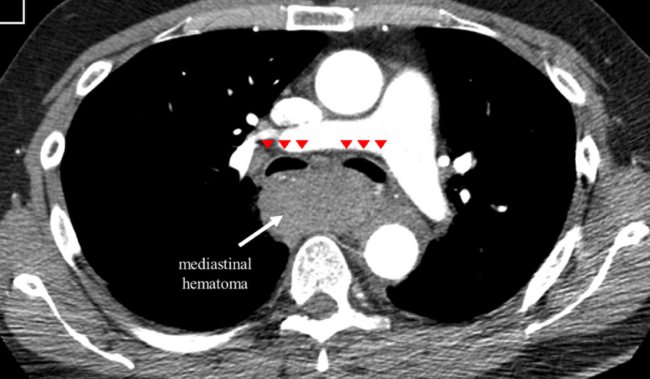

A 65-year-old man who presented with lateral ST-segment-elevation myocardial infarction was referred for primary percutaneous coronary intervention. J-wire and 5.2-Fr JR4 diagnostic catheter progression through right radial artery access was hampered by radial artery spasm and subclavian artery tortuosity. Then, a hydrophilic-coated guidewire was used to assist catheter advancement into the aortic root. Coronary angiography revealed an acute occlusion of the first obtuse marginal artery, which was successfully revascularized with 2 consecutive drug-eluting stents (Video Series). Three hours later, the patient developed symptoms of pleuritic chest pain, dyspnea, stridor, and evolved with shock. Thoracic computed tomography (CT) angiography revealed a large mediastinal hematoma compressing the airway (Figures 1C, 1E and Figure 2). Due to high index of suspicion and after multidisciplinary heart team discussion, an upper limb angiography was performed, which detected perforation of a small collateral branch of the brachiocephalic artery (Figure 1A). The perforation was treated with a single coil embolization, resolving the active bleeding (Figure 1B and Figure 3). Control CT imaging at 2-month follow-up revealed complete resolution of the mediastinal hematoma and airway compression (Figures 1D, 1F).